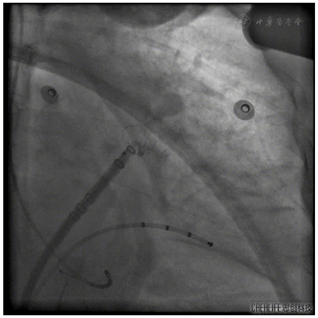

穿刺成功先行房颤射频消融治疗,消融完成后更换左心耳封堵鞘,以猪尾导管保护于RAO30° CAU25°造影,左心耳形态充分暴露,可以观察到心耳属于反鸡翅形状。内部梳状肌较发达,深度较浅。DSA测量开口18mm,深度19mm,与CT测量结果类似,考虑选择24mm watchman封堵器,首选X3轴向进行封堵。术中在猪尾导管的保护下,逆时针旋转输送鞘,尽量将输送鞘送入上叶。稳定输送系统,体外预借2mm深度,送入封堵伞,逆时针旋转稳定输送鞘,术中缓慢释放封堵伞,释放后稳定5分钟后造影提示封堵完全,上缘轻度露肩,行TEE检查未见残余分流,压缩比测量12.5%~21%(图7,图8),经牵拉测试稳定,符合PASS原则,决定释放封堵器,释放后再次造影提示封堵完全(图9)。术后患者顺利清醒,术后6小时检测无心包积液,加用达比加群110mg 2次/天;术后第五天出院。

术后患者一般情况可,术后2月余复查CT(图10)提示左心耳封堵完全,未见残余分流,封堵器位置良好,上缘轻度露肩,未见器械相关血栓发生,遂停用达比加群,予以双联抗血小板药物进行治疗。